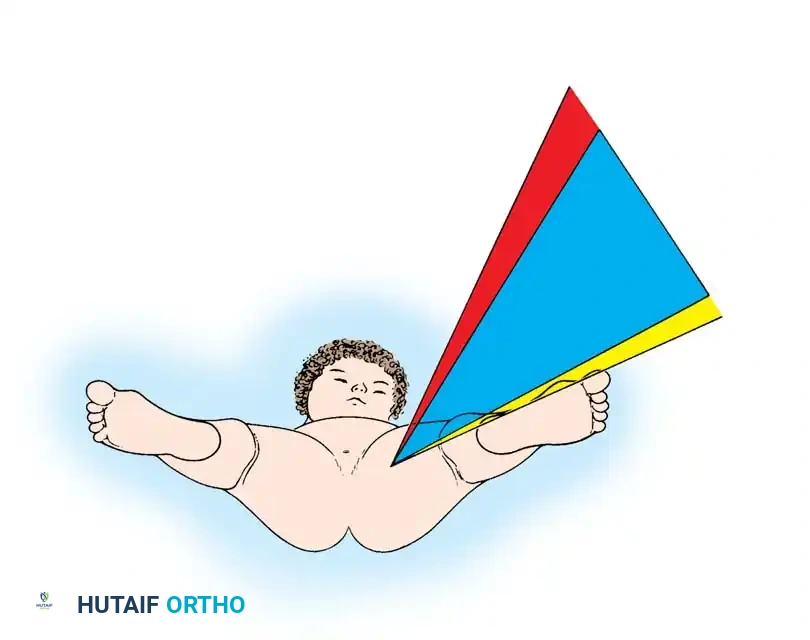

Fig 27-1: Ortolani maneuver for routine screening. The examiner stabilizes the pelvis, places the index and middle fingers over the greater trochanter, and gently abducts the hip.

Fig 27-2: Clinical signs of DDH in an older infant. Note the profound decrease in abduction (A) and the positive Galeazzi sign (B).